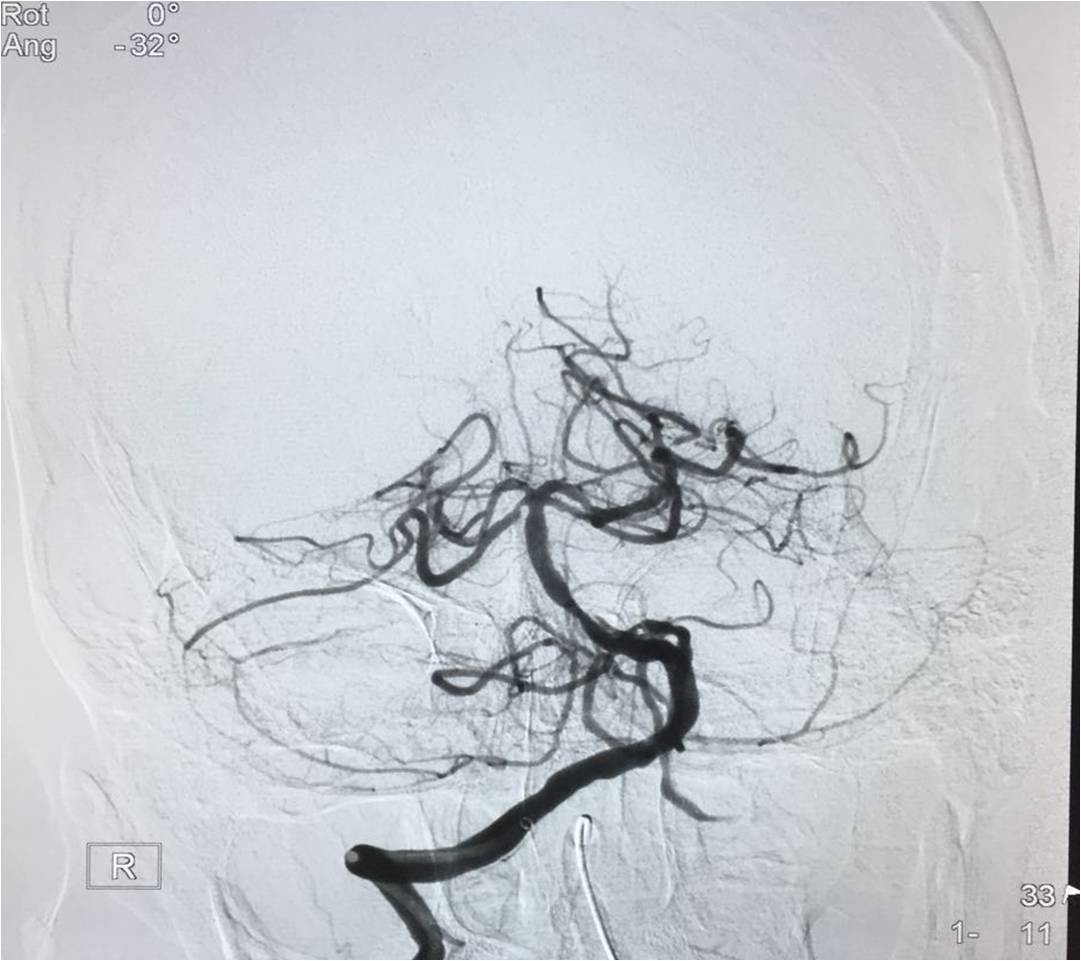

▼行造影明确动脉闭塞部位

▼微导管定位